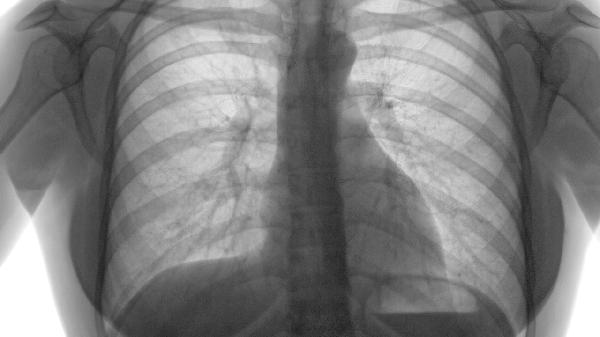

第一秒用力呼气容积FEV1是重要预测指标。FEV1低于35%预计值时,五年死亡率可达40%-60%。吸烟会持续加重气道阻塞,诱发呼吸衰竭。